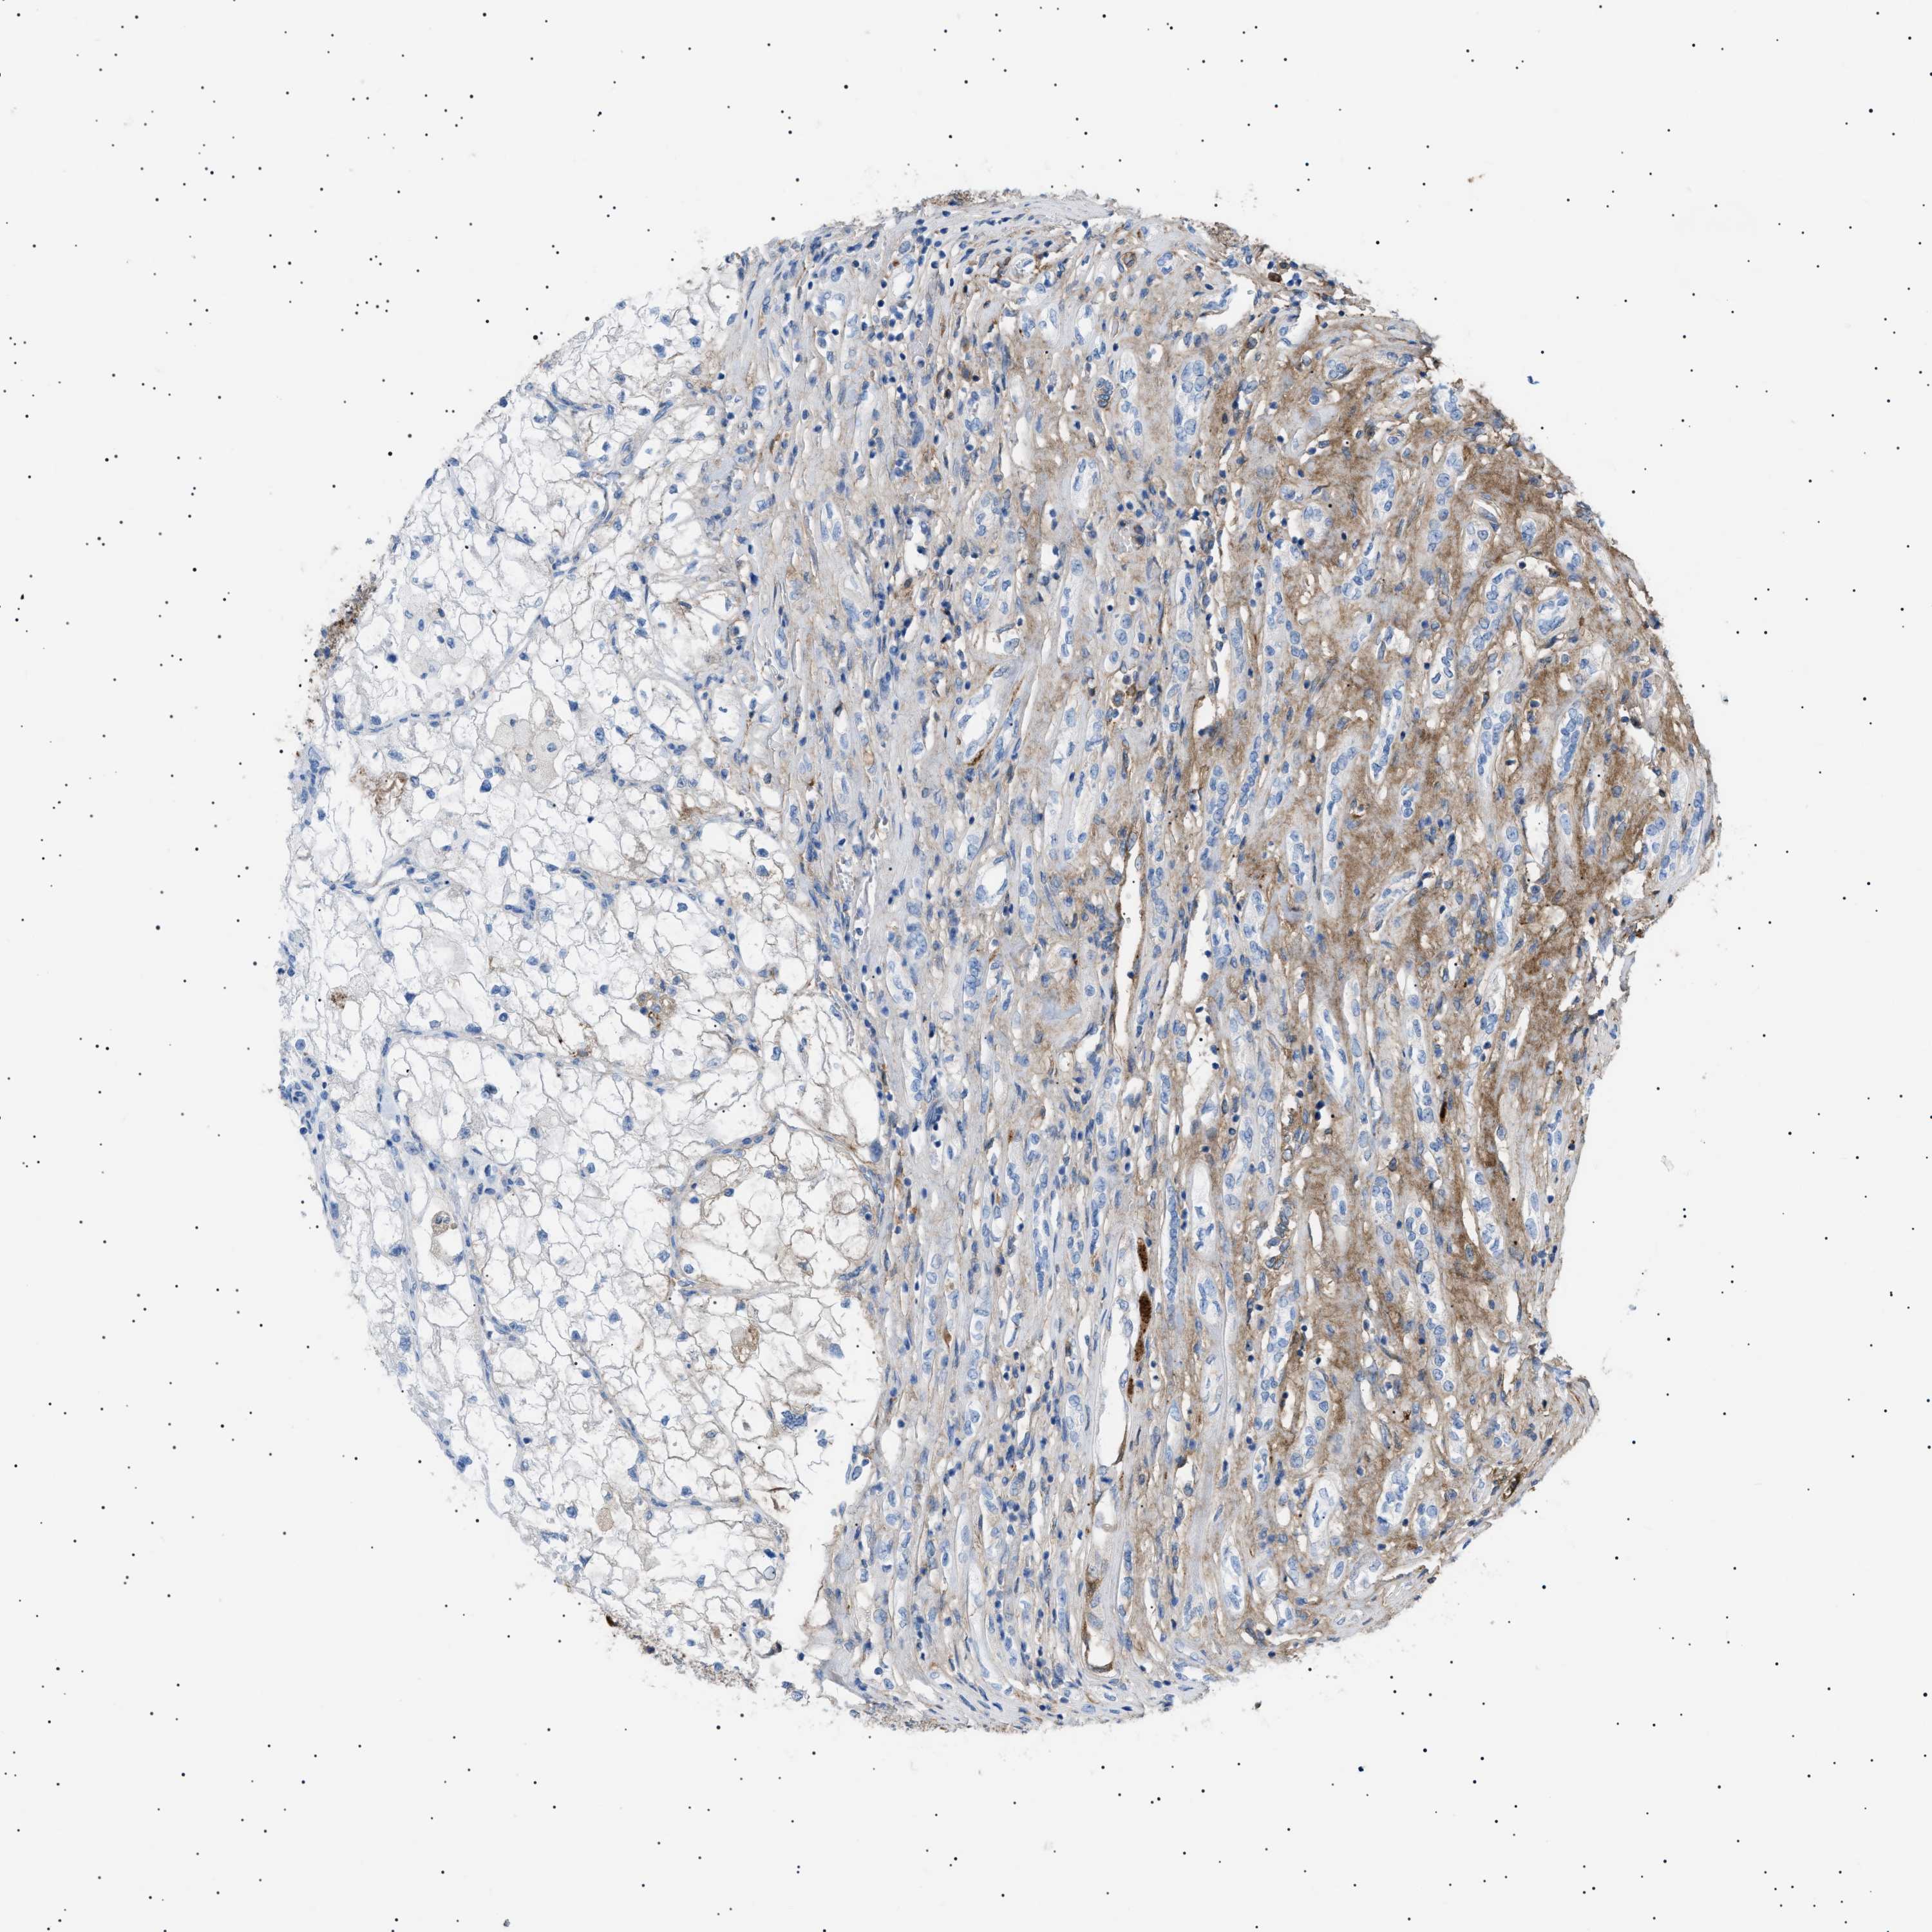

CANCER RENAL CANCER Show tissue menu

KICH TCGA KIRC TCGA KIRC VALIDATION KIRP TCGA PROTEIN RCC CPTAC PROTEIN EXPRESSION